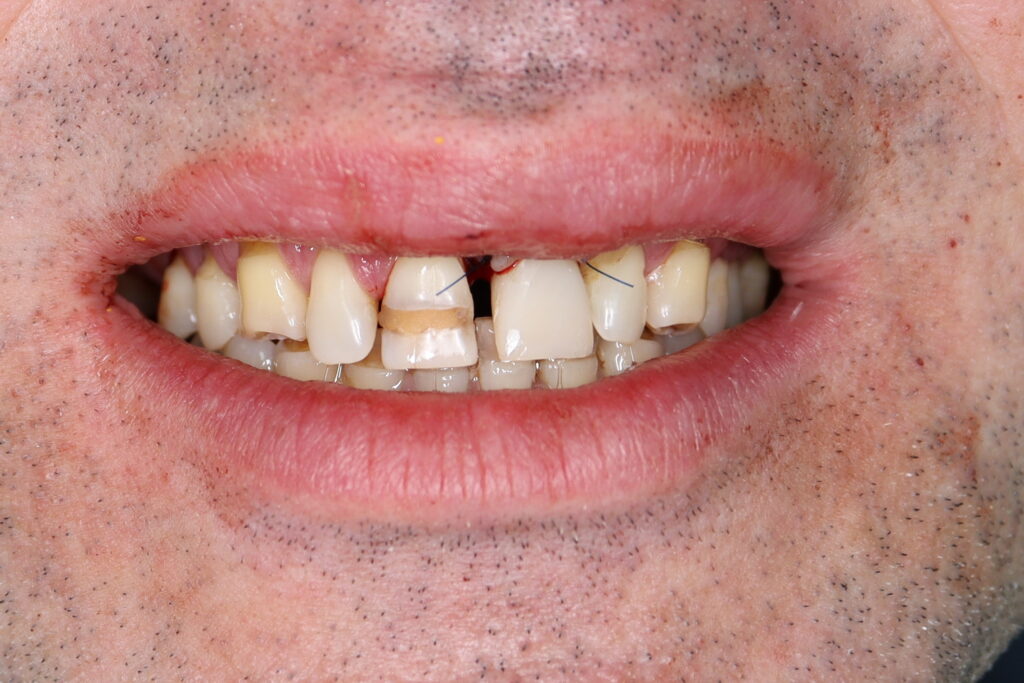

Ситуация до лечения

Пациент обратился с жалобами на эстетические недостатки.

Диагноз: Частичная адентия, клиновидные дефекты, гипоплазия эмали.

пациент до имплантации